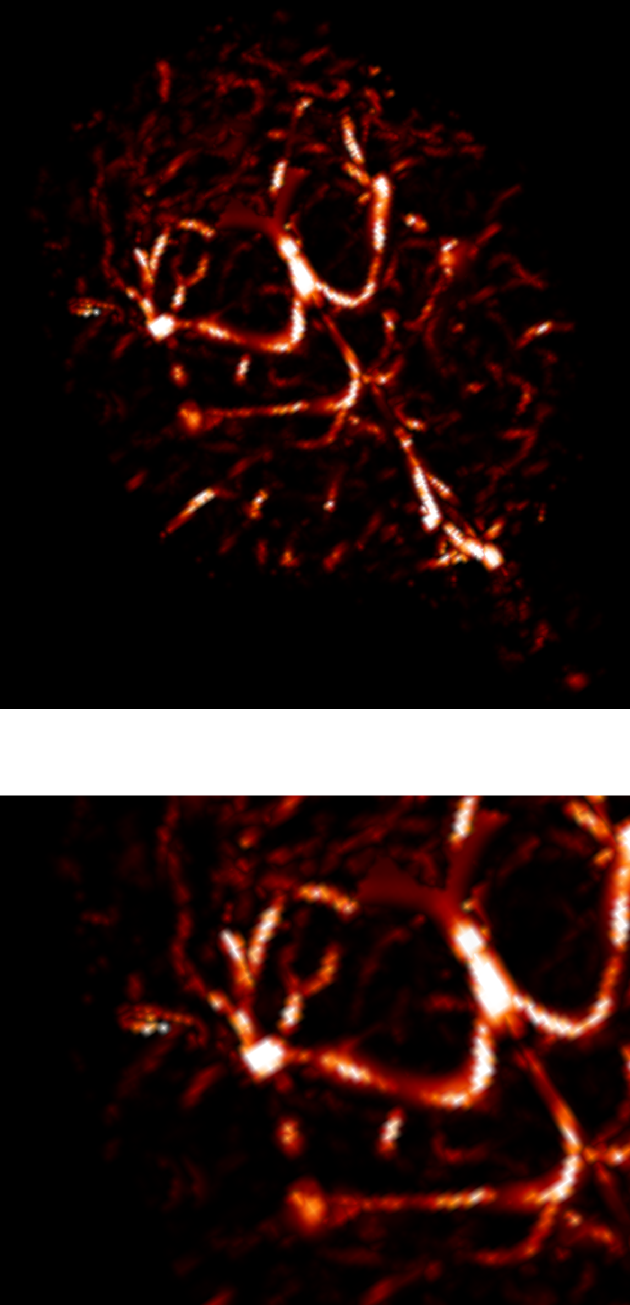

3.2.2 3D angiography

Using the same method as in 2D, namely TSP-sampling and projection onto the set of constraints, we reconstructed volumes from 3D -space. In order to estimate the quality of the reconstructions, we compared the angiograms computed from the 3D images using Frangi filtering [19]. The results are shown in Fig. 3 for acceleration factors (Fig. 3(b,e)) and (Fig. 3(c,f)) and compared to the angiogram computed from the whole data.

Using the strategy described in Part 3.1 the time to traverse -space would be 3.53 s (full acquisition), 3.15 s () and 0.88 s (). The main drawback of TSP-based sampling schemes is that the time reduction is not directly proportional to , in contrast to classical 2D downsampling and reading out along the third dimension. Nevertheless, if the number of measurements is fixed, the TSP-based approach leads to more accurate reconstruction results since the sampling scheme may fit any density [7].

Angiograms shown in Fig. 3 illustrate that one can reduce the travel time in the -space and still observe accurate microvascular structure. If , time reduction is minor (about 10% less), but the computed angiogram is almost the same as the one obtained with a complete -space. It is interesting to notice that with a higher acceleration factor (), the acquisition time is reduced by 75%, but the computed angiogram remains of good quality. The angiogram appears a bit noisier, especially in the pre-injection setting (Fig. 3(c)), but the post-injection image allows recovering Willis polygon and most of the major vessels of the mouse brain (Fig. 3(f)).

| Original (s) | (s) | (s) |

|---|---|---|

| (a) | (b) | (c) |

|

pre-injection

|

|

|

| PSNR=29.0 dB | PSNR=26.6 dB | |

| (d) | (e) | (f) |

|

post-injection

|

|

|

| PSNR=25.5 dB | PSNR=24.1 dB |